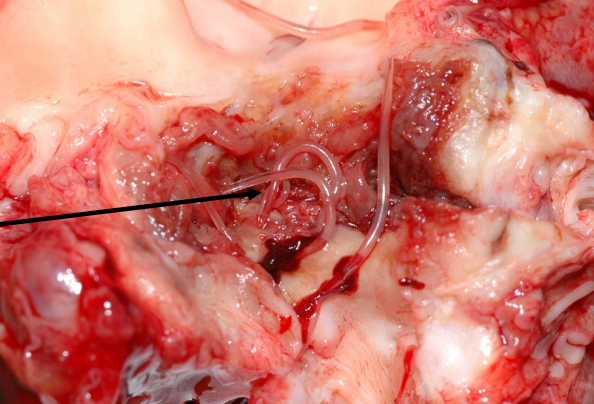

Echinococcus multiocularis